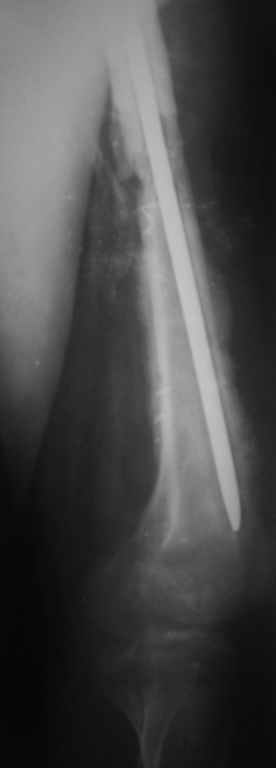

если первые 4 месяца послеоперационного периода проходил без проблем, но на 5 месяце появились боли в дистальном отделе бедра и температура, т.е. симптомы медуллярного инфицирования (рис №3, №4).

Замена реконструктивного штифта “Custom made Nail” с антибиотиком (рис №5, №6),

после промывки канала с рассверливанием внутреннего кортекса, через 4 недели антибиотический штифт удалили, оспалителный процесс остановлен и бедро сросся.